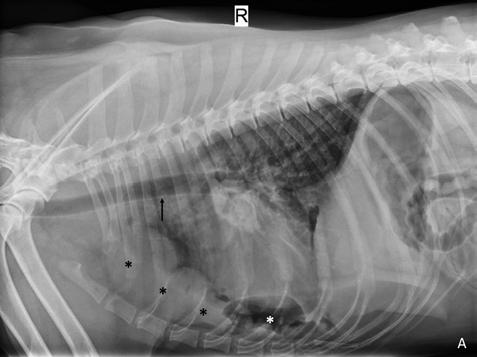

Se realiza radiografía de tórax (Fig. 1) que revela car-

diomegalia generalizada severa, índice de Buchanan de 15 cuerpos vertebrales, que puede corresponder a un severo aumento de las cámaras cardiacas, o a la presencia de líquido pericárdico. Se observa, además, un patrón pulmonar intersticial perihiliar, compatible con edema pulmonar, foco de neumonía o hemorragia pulmonar.

M. López,1 V. Fernández,2 J. Engel3 1Servicio de cardiología y diagnóstico por imagen. 2Servicio de cirugía. Laclinicaveterinaria. c/Marroquina 26. 28030 Madrid. 3Servicio de cardiología. ANICURA-Benipeixcar Hospital Veterinario. Avinguda de la Constitució 68, bajo izq. 46009 Valencia. ANICURA-San Francisco Hospital Veterinario. c/ Sant Francesc 65. 12500 Vinaròs (Castelló). ANICURA-San Vicente Hospital Veterinario. c/ Veterinario Manuel Isidro Rodríguez García 17. 03690 San Vicente del Raspeig (Alicante). Figura 1. Radiografía lateral de tórax en la que se observa cardiomegalia generalizada, VHS 15. Patrón alveolar intersticial compatible con edema pulmonar. Patrón vascular mixto y patrón bronquial en lóbulos caudales, compatible con bronquitis crónica, mineralización por degeneración senil.

En el caso que presentamos podemos confirmar cardiomegalia severa y edema pulmonar dado que el estudio radiológico del tórax permite establecer el tamaño cardiaco y valorar el patrón pulmonar. La insuficiencia cardíaca congestiva izquierda se caracteriza por un patrón intersticial, que puede evolucionar a patrón alveolar en la región perihiliar que tiende a distribuirse hacia caudodorsal, característico del edema pulmonar cardiogénico, patrón vascular venoso.